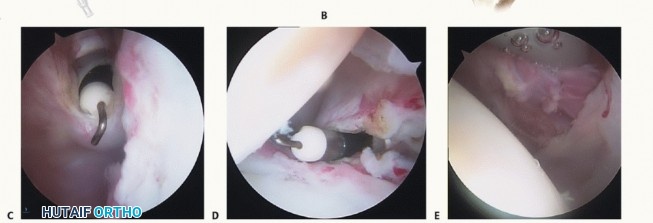

The challenging aspect of arthroscopic capsular release is entering the contracted joint while avoiding iatrogenic articular injury ( TECH FIG 1A ).

We establish the posterior arthroscopic portal slightly higher than normal ( TECH FIG 1A-C ).

TECH FIG 1

• It is often difficult to enter a shoulder with significant capsular contraction and scarring.

A.

The posterior portal (

a

) is established higher than normal to lessen the risk of iatrogenic articular damage. The lateral (

b

) and anterior (

c

) portals are established using the outside-in technique with an 18-gauge spinal needle.

B.

Sterile normal saline is injected into the glenohumeral joint. This causes distention, which lessens the risk of iatrogenic articular damage and verifies the portal position. Backflow of saline through the spinal needle ensures entry into the joint as opposed to soft tissue.

C.

The anterior capsule is visualized by the arthroscope from the posterior portal and a radiofrequency device is placed through the cannula anteriorly to remove synovium and create a potential working space.

D

. Entering at or above the biceps with the anterior cannula is typically possible.

E.

The biceps can be displaced inferiorly and the rotator interval can be ablated to relax the joint and allow further release inferiorly.

F.

Forced entry with poor visualization can result in significant osteochondral injury, as depicted in this image.

HH

, humeral head.

An 18-gauge spinal needle is inserted into the joint and insufflated (usually 10 to 15 mL in a contracted joint) with sterile saline ( TECH FIG 1B ).

Entry into the joint can be confirmed by noting backflow of saline from the spinal needle.

This step ensures proper portal placement and also distends the joint, thus lessening the risk of iatrogenic articular injury ( TECH FIG 1F ).